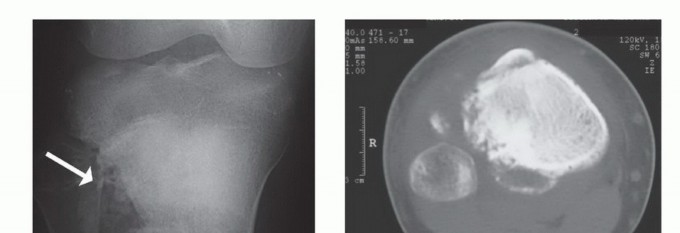

- الأشعة السينية (X-rays): هي الخطوة الأولى، وتُظهر التغيرات في بنية العظم، مثل التدمير العظمي، أو تكوين العظم الجديد، أو رد فعل السمحاق.

- التصوير المقطعي المحوسب (CT Scan): يُستخدم لتقييم التدمير العظمي بشكل أفضل، وتحديد وجود أي نقائل في الرئتين أو أجزاء أخرى من الجسم.